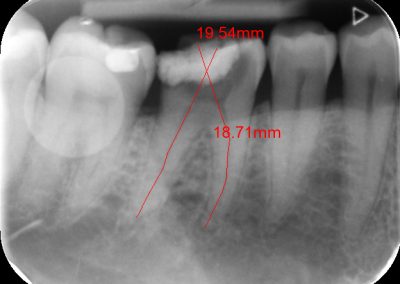

During the consultation, the dentist will first listen to your concerns and carry out appropriate tests to identify the right tooth that is causing pain. As a part of the diagnosis, your dentist will carry out various clinical tests to identify the right tooth and will take some radiographs which can aid in the diagnosis.

An access cavity is placed on the surface where the patient bites, to reach the root canals of the tooth. Once all the canals are identified, small files are used to remove the infected pulp.

Files of different sizes are used to eliminate bacteria and infection and to shape the canals. The canals are disinfected thoroughly with irrigants and later the canals will be sealed in 3 dimensions with a special medicament called gutta-percha to prevent reinfection of the tooth and the access cavity will be sealed with a temporary filling.